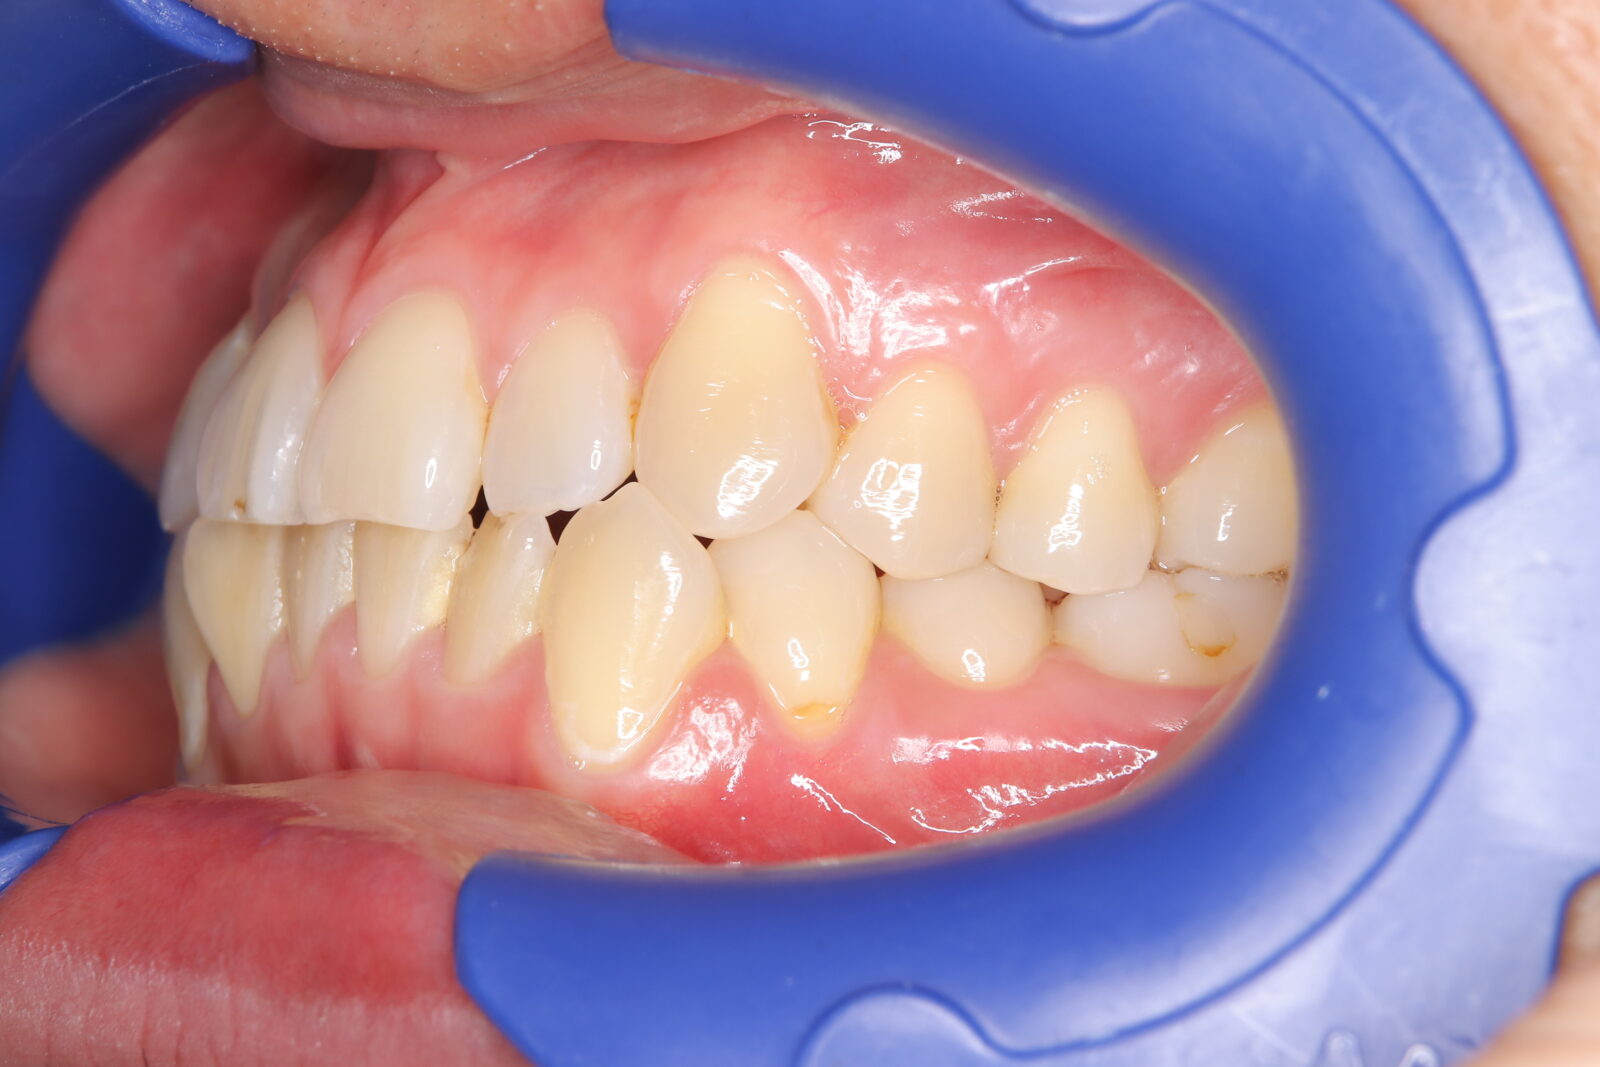

インビザライン(全体矯正)+ホワイトニングコース+セラミック治療の症例

過去にワイヤー矯正で治せなかったクロスバイト。インビザライン(全体矯正)とホワイトニングとセラミック治療で綺麗な笑顔へ。

・費用:726,000円(税込) ※ホームホワイトニングと右上6番ジルコニアクラウン含む

・治療期間:15ヶ月

・通院回数:10回

・32歳女性

-リスクと副作用-

・長時間マウスピースを装着するため、むし歯や歯周病のリスクがある。治療後はリテーナーを装着しないと後戻りしてしまうリスクがある。

・ホワイトニング剤の影響で知覚過敏が起こる可能性がある。色が徐々に戻る可能性がる。

・セラミック:過度な衝撃によって割れることがある。